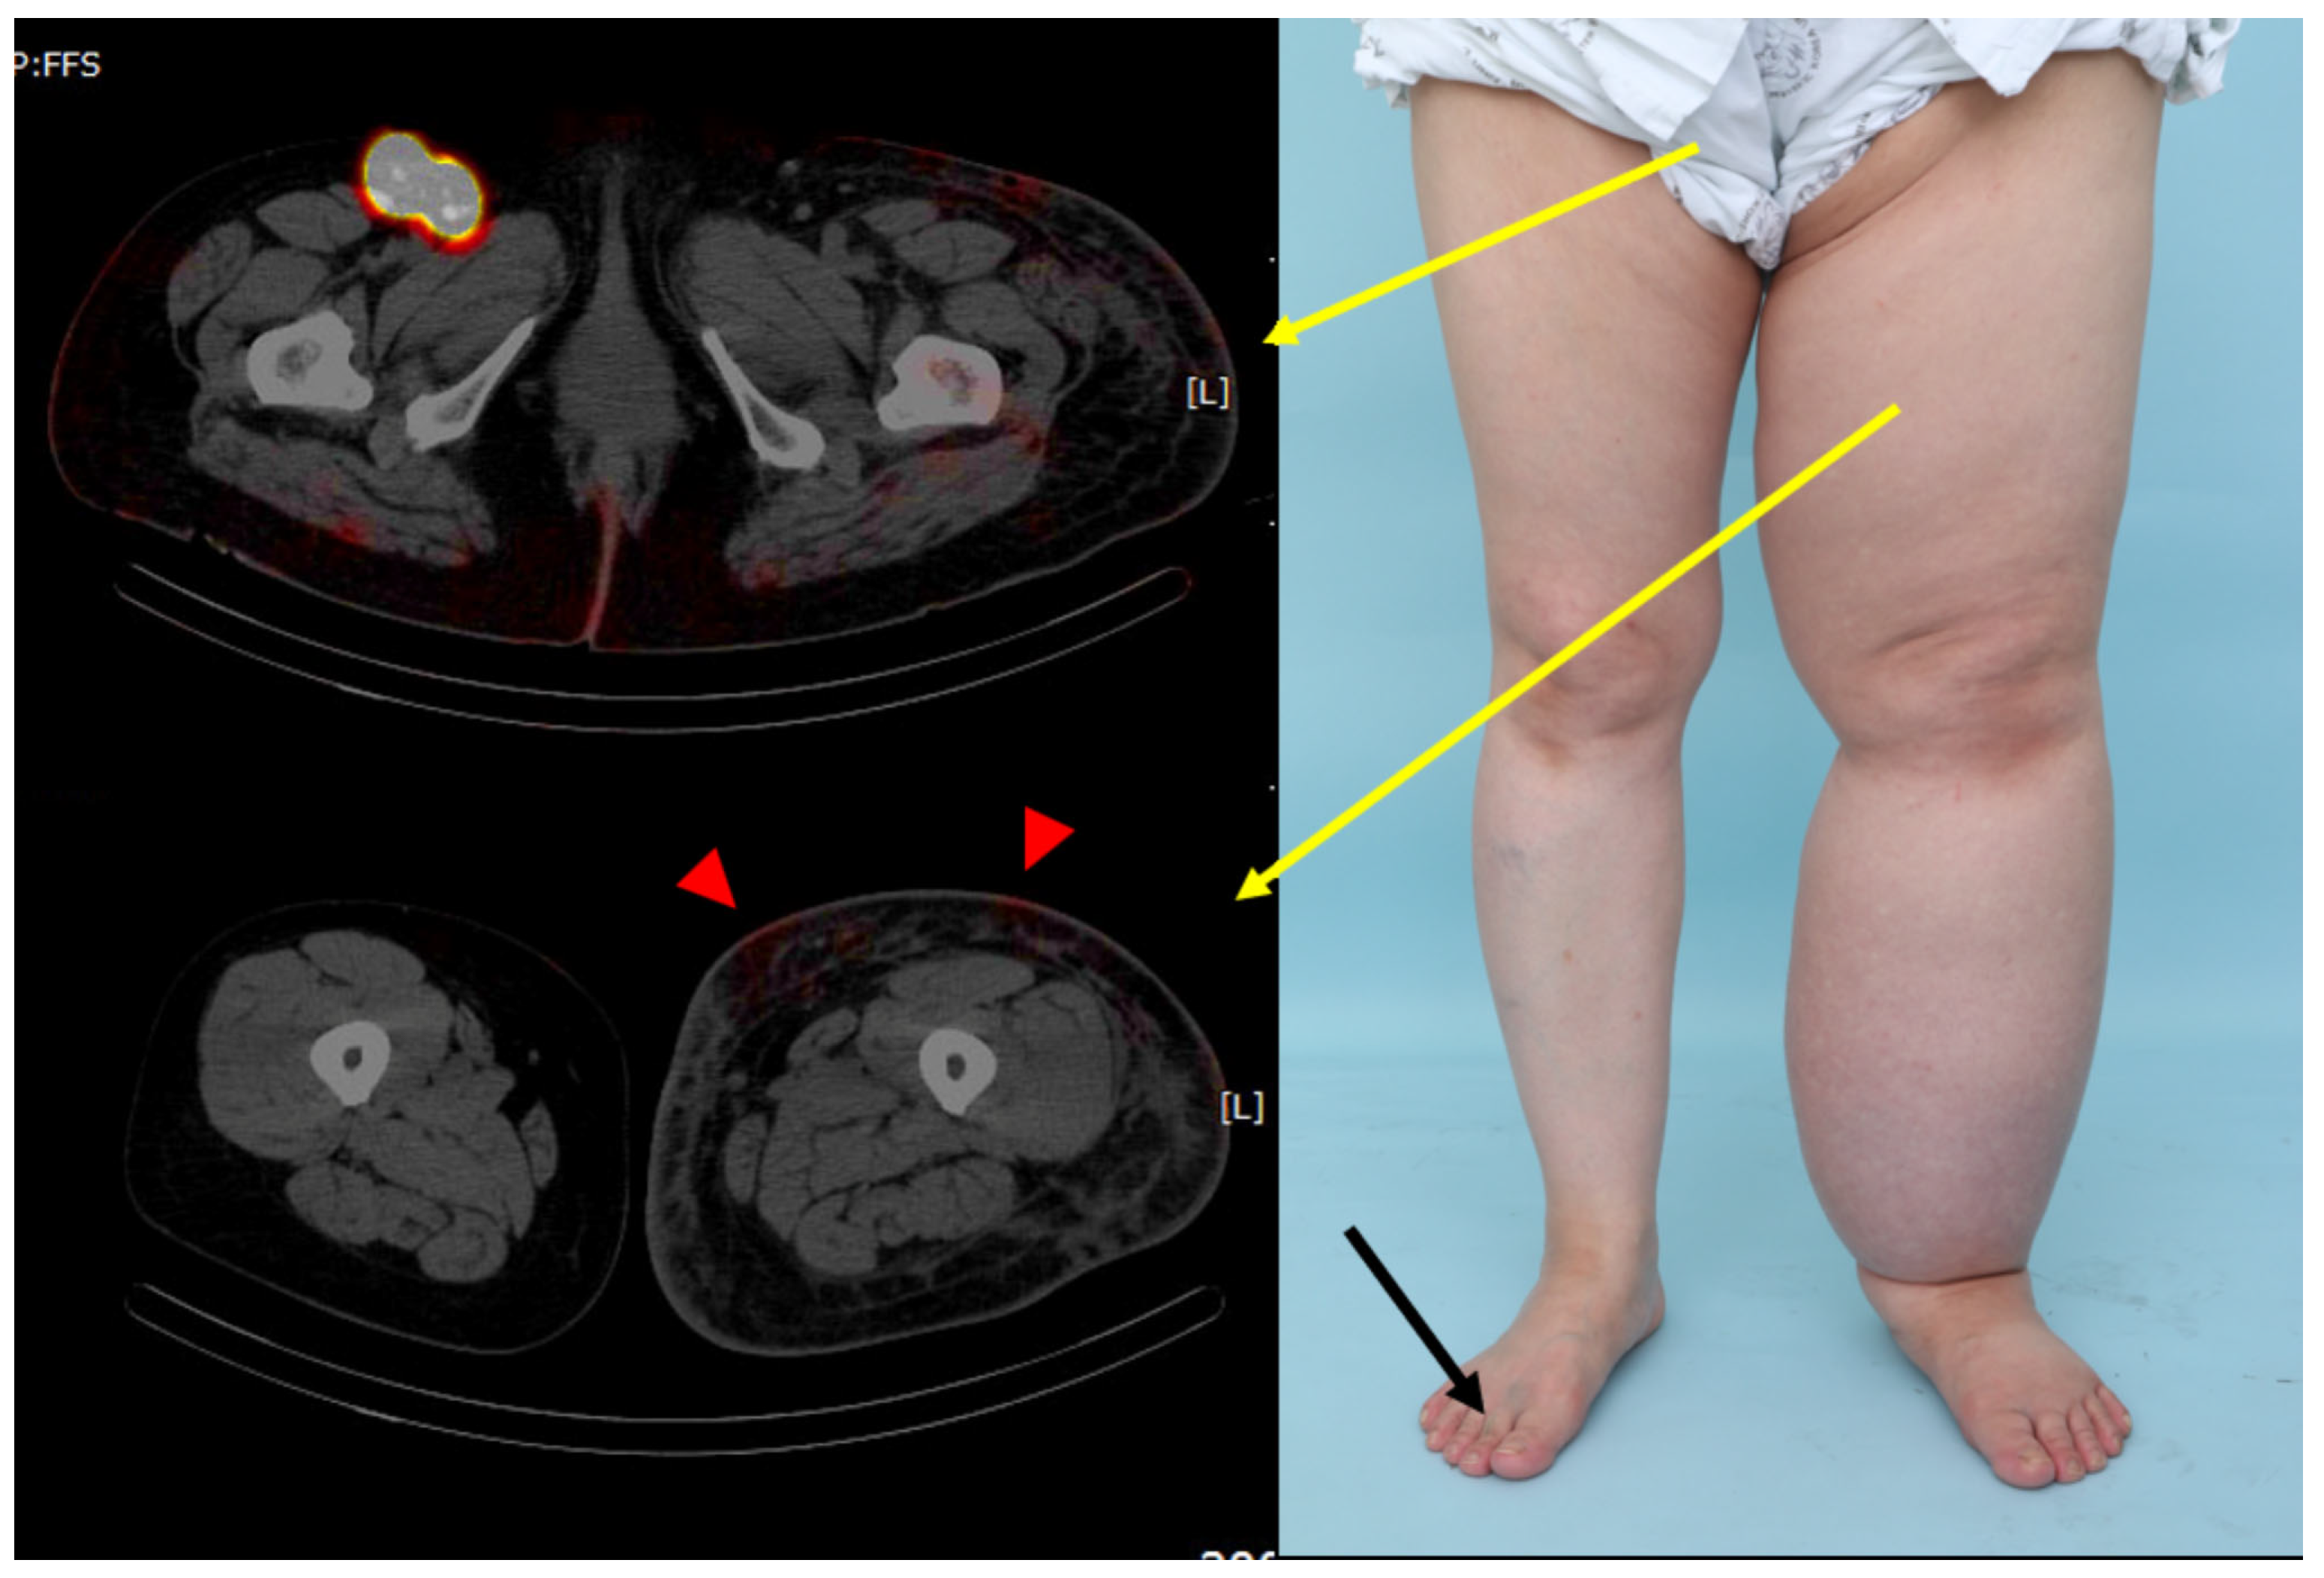

| Negative finding (Neither pelvic retention nor retrograde lymphatic flow) | 3 (30.0%) |

| Pelvic retention only | 1 (10.0%) |

| Lower limb retrograde lymphatic flow only | 0 |

| Pelvic retention with lower limb retrograde lymphatic flow | 6 (60.0%) |

| Extent of lower limb retrograde lymphatic flow | |

| Thigh | 6 out of 6 (100%) |